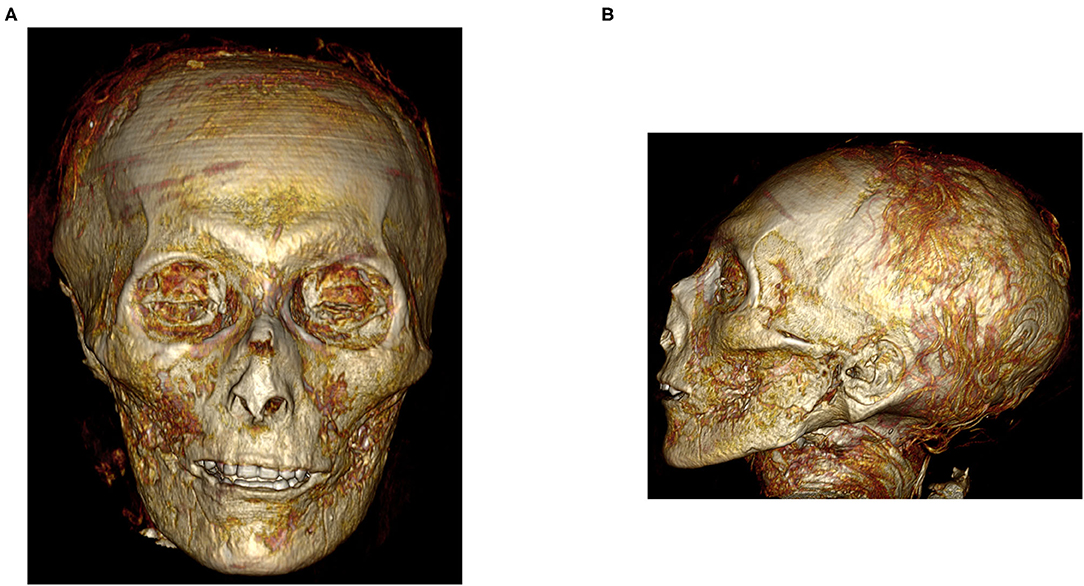

No fue solo una tomografía, sino varias con las que los arqueólogos descubrieron varias cosas que hasta ahora desconocían del faraón y de su entierro. Por ejemplo, lograron saber como era su rostro, el cual había estado envuelto durante miles de años, informaron en el estudio que se publicó en la revista Frontiers in Medicine.

Al respecto, también la doctora Sahar Saleem, profesora de radiología en la Facultad de Medicina de la Universidad de El Cairo y principal autora del estudio, dijo a la BBC que lo que más llamó su atención fue ver los rasgos faciales del faraón, los cuales, de acuerdo a la experta, se parecen mucho a los de su padre, Ahmose I, el primer faraón de la dinastía XVIII de Egipto: un mentón estrecho, nariz pequeña y estrecha, cabello rizado y dientes superiores ligeramente protuberantes.

Por otra parte, ella y un grupo de antropólogos lograron saber que Amenhotep I medía aproximadamente un metro con 69 centímetros de alto y que tenía más o menos 35 años de edad cuando murió.

De acuerdo a la doctora Saleem, las tomografías y observaciones mostraron que el faraón estaba en buenas condiciones físicas, así como en un buen estado de salud cuando murió. Incluso, indicaron que no tenía heridas o alguna desfiguración por alguna enfermedad.

Es por esto que los antropólogos creen que Amenhotep I pudo haber muerto por una infección o virus. Además, estas investigaciones lograron descubrir algunos detalles sobre su momificación y entierro, como que fue el primer faraón en tener los antebrazos cruzados sobre el pecho y que, extrañamente, no se le extirpó el cerebro, algo normal en el ritual de momificación.

Por otra parte, supieron que sacerdotes de la dinastía XXI, la cual gobernó unos cuatro siglos después de su muerte, lo repararon, ya que posiblemente fue víctima de ladrones de tumbas. Sí, por ejemplo, se dieron cuenta que fijaron su cabeza y el cuello, los cuales estaban desprendidos del cuerpo.

Por último, la doctora señaló que el faraón lleva 30 amuletos y un cinturón dorado con cuentas de oro, los cuales no se los quitaron sacerdotes para otros faraones, algo que llegó a pensarse pero que ahora ya se descartó.